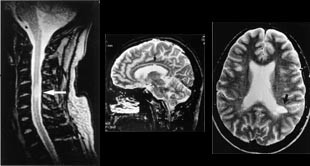

MR gir verdifull informasjon hos pasienter med degenerative lidelser i columna. En av de store fordelene ved MR er at bein og bløtdeler kan demonstreres i samme bilde, men atskilles pga. forskjellige signaler. Foreløpig kan det være et problem at oppløsningen i bildene ikke er så god som i konvensjonelle røntgenbilder. Enkelte detaljer kan derfor fremstilles bedre ved konvensjonelle radiologiske metoder, f.eks. rotskjeder ved myelografi. Prolaps kan som oftest fremstilles tilfredsstillende med CT (19), men i de fleste tilfeller er MR-bildene lettere å tolke (fig 6) (5).